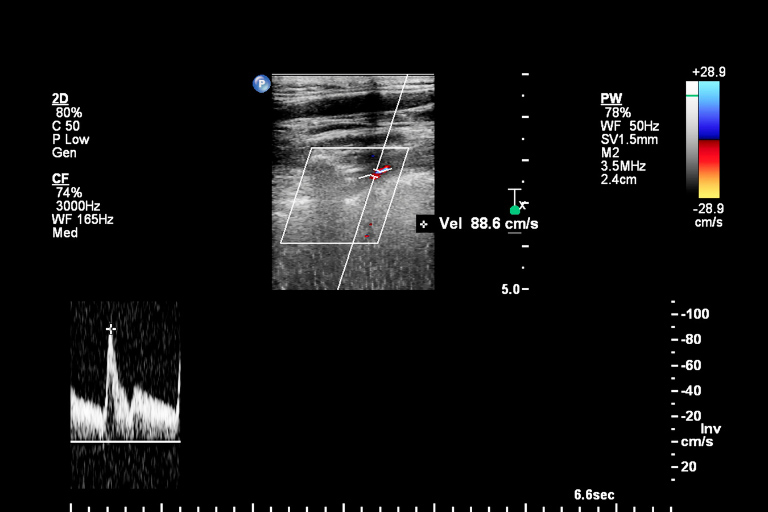

In der Angiologie steht bei Untersuchungen eine Ultraschallfunktion klar an der Spitze: Die Duplexsonographie kombiniert das Beste aus Dopplersonographie und regulären Ultraschalluntersuchungen und liefert klare Bilder von Gefäßstruktur und Blutfluss in Echtzeit. Das unsere Ultraschallgeräte für Gefäßkliniken mit funktionellen und hochwertigen Duplex-Programmen ausgestattet sind, ist für uns also eine Selbstverständlichkeit. Sinnvolle Extra-Funktionen und Speichermöglichkeiten für regelmäßige Arbeitsabläufe machen die Ultraschall-Diagnostik von Venen und Arterien zu einer Bereicherung für Ihre Klinik.

Klare Bilder von Struktur und Blutfluss

Volle Farbwiedergabe für genaue Diagnostik